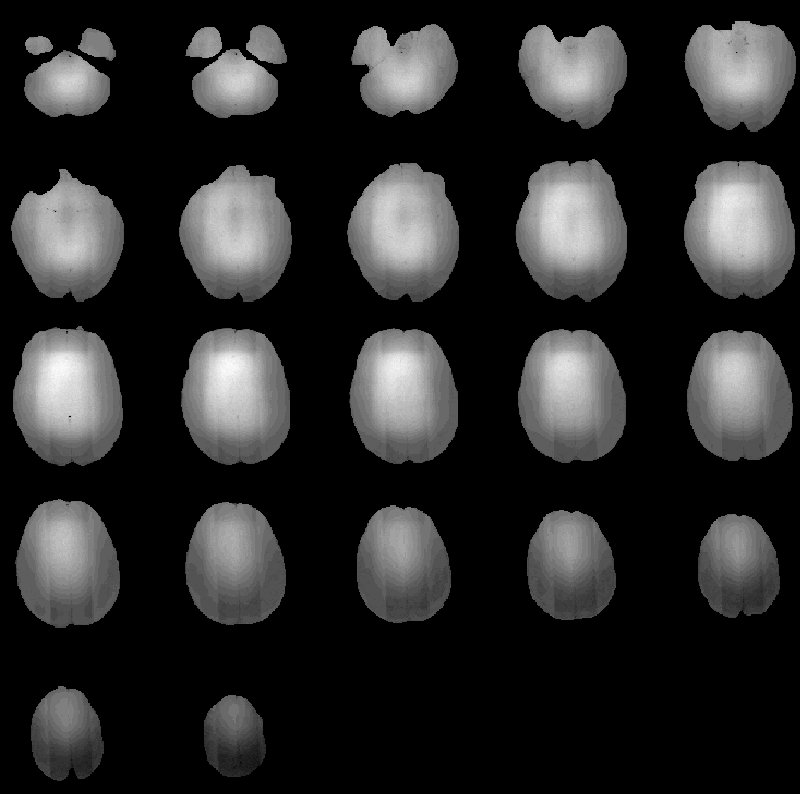

The Correct Intensity process again reduces the intensity variation due to RF inhomogeneity in Data Set 3. The detected inhomogeneity is shown in Figure 8.32. Figure 8.33 obviates the correction to slice 16.

Figure 8.32: RF inhomogeneity detected in

MRI Data Set 3.

Figure 8.33: Slice 16 of MRI Data Set 3 (a) before

and (b) after RF correction.